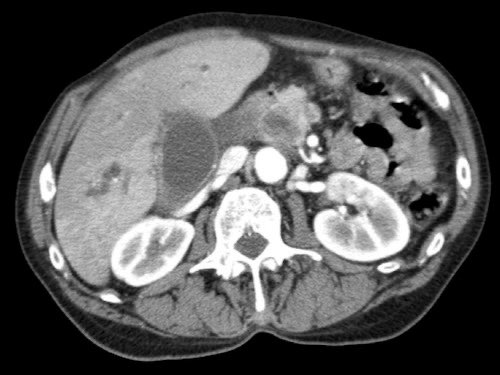

Đánh giá giai đoạn tại chỗ cần được thực hiện bằng CT tụy chất lượng cao, bao gồm thì động mạch muộn và thì tĩnh mạch cửa.

Ung thư biểu mô tuyến tụy thường biểu hiện là một khối giảm tỷ trọng, kém mạch máu, được nhận thấy rõ nhất ở thì động mạch muộn. Đây cũng là thì tốt nhất để đánh giá giải phẫu động mạch nhằm phát hiện các biến thể và hẹp mạch.

Thì tĩnh mạch cửa là tốt nhất để phát hiện di căn gan cũng như phát hiện hẹp và xâm lấn tĩnh mạch.